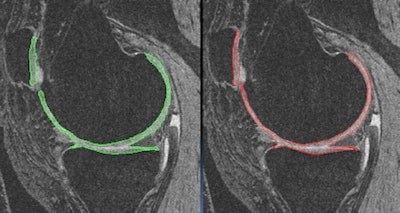

CAD tools can also be quite useful in segmenting knee cartilage on MRI scans. In recent research performed at the University of Pittsburgh, a semiautomated method was 10 times faster and more reproducible than manual segmentation, Bae said.

| Semiautomated segmentation of knee cartilage (left) was found to closely agree with a manual delineation method (right), and was also more efficient and reliable. |